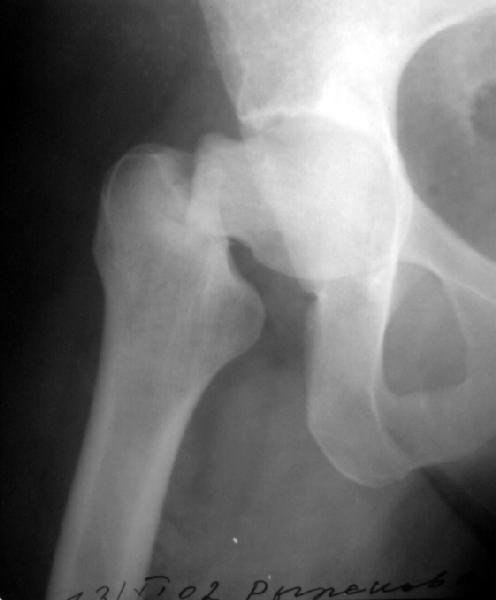

Сегодня сделали, прилагаю. Качество не очень, но положение отломков видно.

It looks like there is an early fatigue (stress) fracture of the opposite hip as well. I would fix both hips with screws, then get a bone mineral density and other endocrologic work-up

?????Is there a lesion on the opposite neck too!!!!

Напоминаю, что упала больная 5 ноября, но до этого несколько месяцев жаловалась на боли в тазобедренном суставе. А вообще "что-то не то" с

этой областью было года два. За все это время уменьшения амплитуды движений, с ее слов, не было. И вот сегодня прислали ее снимок,

сделанный 1 ноября, до есть за 4 дня до падения. Вроде есть там что-то типа лоозеровской зоны.

Может, все-таки усталостный перелом?